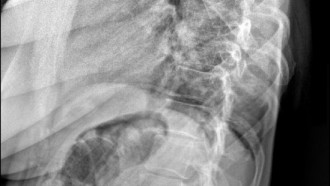

Osteoporoza nie wywołuje żadnych objawów. Jest chorobą charakteryzującą się niską masą kostną. W osteoporozie kość staje się porowata, zrzeszotniała i krucha. Podczas upadku tkanka kostna ma zwiększoną podatność na złamania. Złamania osteoporotyczne dotyczą całego kręgosłupa, kości przedramienia oraz szyjki kości udowej. Złamania mogą wystąpić również w innych lokalizacjach. Problem niskiej masy kostnej może dotyczyć każdego, niezależnie od wieku, płci i pochodzenia. Wczesne diagnozowanie i wdrożenie leczenia jest kluczowe i może pomóc zachować kondycję oraz sprawność pacjentów przez długie lata.

Densytometria jest najlepszą dostępną metodą diagnozowania osteoporozy, również w jej stadium bezobjawowym, czyli przed wystąpieniem złamania kości lub kręgosłupa. Służy także ocenie efektywności prowadzonego leczenia. Jest to rodzaj badania wykorzystującego niewielkie dawki promieniowania rentgenowskiego i ma na celu określenie gęstości mineralnej kości (BMD - Bone Mineral Denstity)

Wynik badania jest podawany w g/cm2 i określa gęstość tkanki kostnej w ocenianym obszarze. W diagnostyce osteoporozy największym znaczeniem klinicznym charakteryzuje się densytometria kręgosłupa lędźwiowego oraz densytometria szyjki kości udowej. W oparciu o wartości wskaźnika T, WHO opracowało kategorie diagnostyczne osteoporozy. Wartość wskaźnika od +1 do -1.0 oznacza normę, pomiędzy -1.1 a -2.4 osteopenię, a od -2,5 lub mniej osteoporozę. Wyniki badań dostępne są na stronie multidiagnostica.lab-online.pl